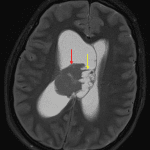

MRI

- Heterogeneous mass in the body of the right lateral ventricle measuring 3.8 x 3.4 x 3.8 cm with a solid component laterally and multiple cystic components medially, broadly contacting the septum pellucidum

- The solid component is isointense on T2, mildly hyperintense on FLAIR, and demonstrates diffuse restricted diffusion and mild patchy enhancement

- Associated right lateral deviation of the septum pellucidum and mass effect on the third ventricle with resultant obstructive hydrocephalus involving the lateral ventricles and anterior aspect of the third ventricle